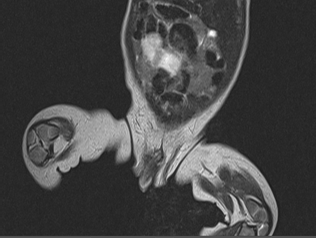

При поражении зоны эпифиза выявлялись патологические изменения суставных структур, нарушение их формы, уменьшение толщины, «изъеденность» хряща, признаки остеосклероза субхондральной зоны. На поздних сроках заболевания секвестры отчетливее определяются на КТ, МРТ несколько уступает в визуализации кортикального слоя кости. У пациентов с метаэпифизарным остеомиелитом в возрасте от 0 до 3 лет выполнено 21 исследование (21,6%). МРТ проводилось в 3 случаях при септической форме заболевания. В 10 (47%) случаях МРТ-исследование использовалось в качестве уточняющей методики в интрамедуллярную фазу на 1-3-и сутки от момента поступления при недостаточной информативности УЗ и рентгенологического методов. В 8 (38%) случаях МРТ применялось при поступлении пациентов на 4-7-е сутки заболевания (рис. 3, 4).

Рис. 3. Томограмма (МРТ) тазобедренных суставов. МЭО левой бедренной кости. 3-и сутки